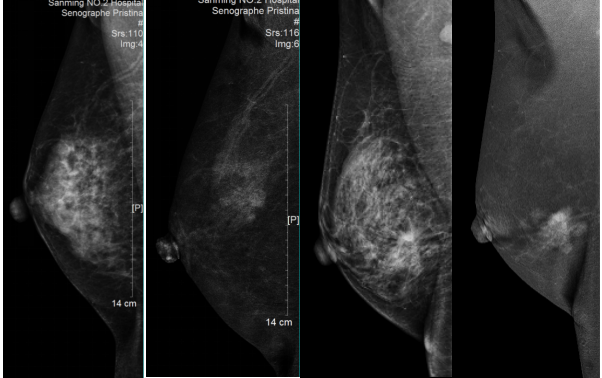

是在乳腺数字摄影的基础上使用对比剂的一项新的检查技术。它通过静脉注射对比剂然后以减影的方式有效消除正常乳腺组织重叠对病灶的遮盖,凸显肿块真实形态、边界,并提供病灶的血供信息,有利于乳腺良、恶性疾病的辨别,提高疾病检出率及准确率。减少了患者不必要的穿刺及带来的经济损失、心理负担。

第1、3张图片均为没有增强前的图片,无法清楚显示病灶;第2、4张为数字能量增强摄影减影后图片,不仅能明确病灶范围、大小及边界,而且能反映肿瘤的血供比较丰富,还可以发现普通摄影中被腺体掩盖的病灶。